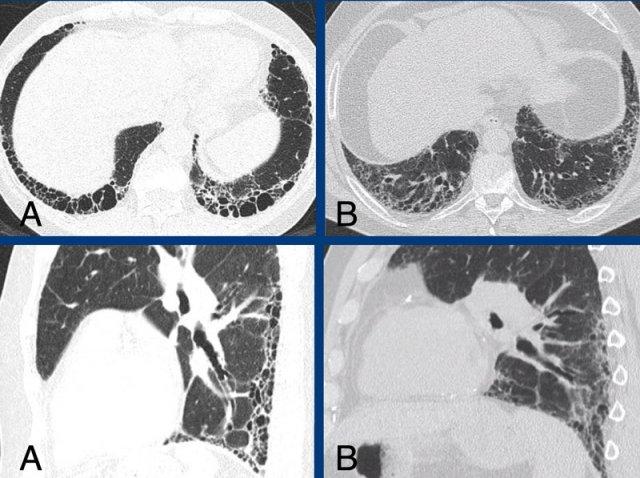

Các hình ảnh cho thấy tổn thương xơ hóa ưu thế ở vùng đáy phổi và dưới màng phổi trong A, so với tổn thương xơ hóa ưu thế ở vùng đỉnh phổi và trung tâm trong B.

Subpleural dominant (A), subpleural sparing (B), and peribronchial dominant (C) patterns of fibrosis.

Typical fibrotic hypersensitivity pneumonitis showing diffuse non-basal dominant (A), peribronchial orientated ground-glass and mild fibrotic changes with mosaicism (A and B), and expiratory air trapping (C).

HP mạn tính xơ hóa điển hình được đặc trưng bởi xơ hóa quanh phế quản với các mức độ kính mờ khác nhau và suy giảm khảm rõ rệt do sự bảo tồn của các tiểu thùy thứ cấp.

Bẫy khí thì thở ra do tắc nghẽn đường thở nhỏ là một dấu hiệu đặc trưng.

Xơ

hóa có thể có phân bố ngẫu nhiên hoặc lan tỏa, hoặc ưu thế ở vùng phổi giữa hoặc trên với tương đối ít tổn thương ở vùng đáy phổi.